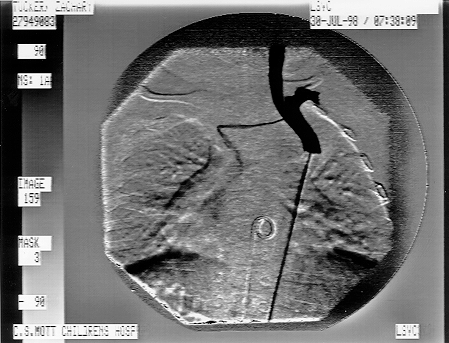

This Shows The Small Communicating Vein Between His Two Superior Vena Cavas